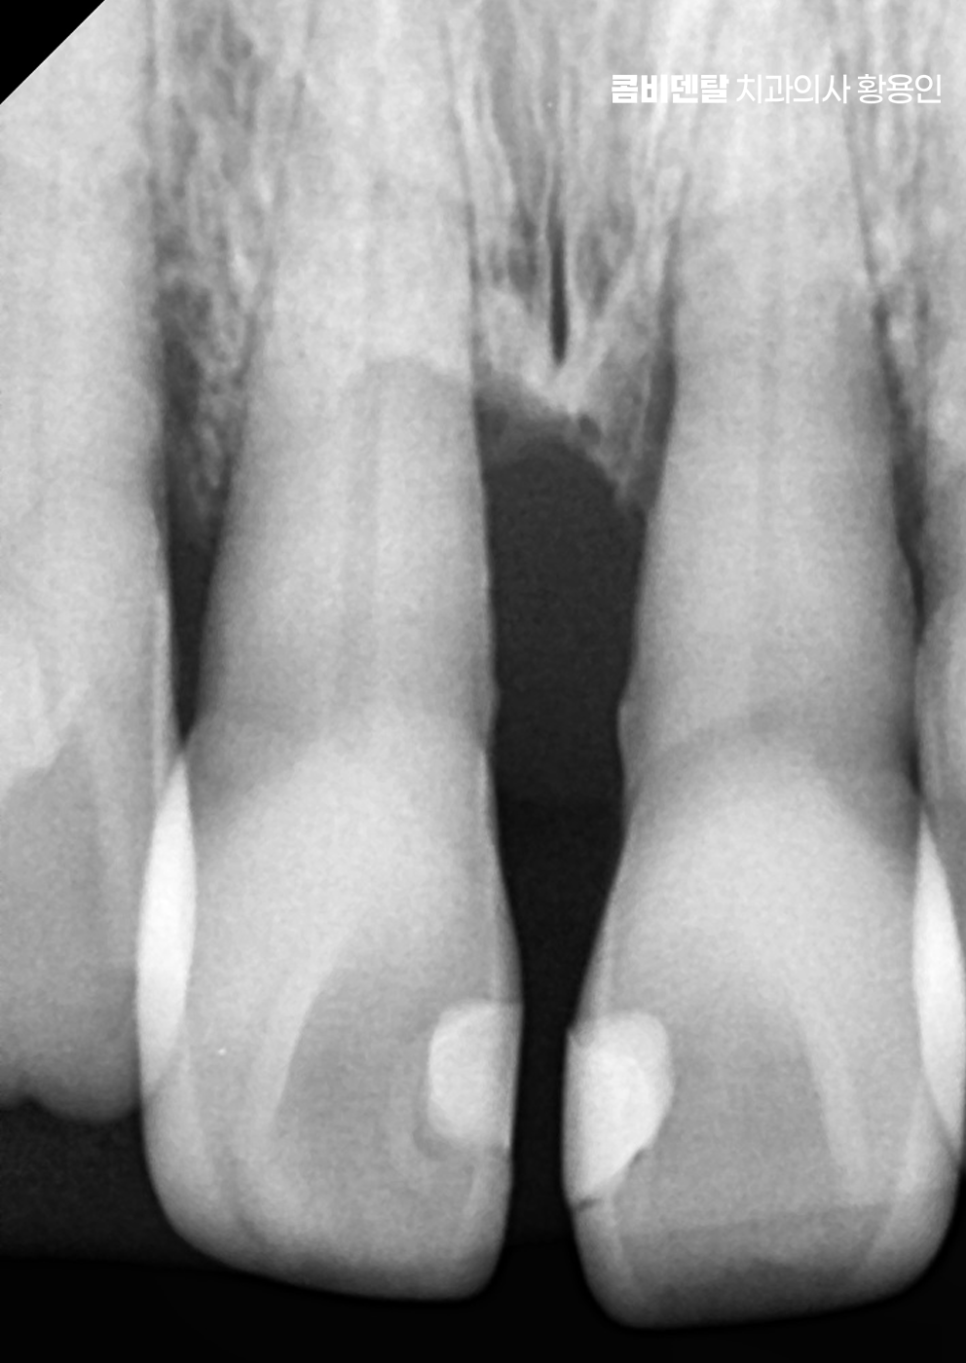

치아 사이가 벌어지는 현상은 보기에는 단순한 틈처럼 느껴질 수 있지만 그 원인이 치주질환 때문이라면 단순히 공간만 메우는 식의 접근으로는 해결되지 않으며 치주질환이라는 건 치아를 지탱하고 있는 잇몸과 치조골, 그러니까 잇몸 뼈 자체가 서서히 무너져가는 질환이기 때문에, 그 과정에서 심하면 치아가 흔들리고, 치아 사이의 지지가 약해지면서 점점 틈이 벌어지게 되며 이 틈은 시간이 지나면서 점점 더 넓어지고 깊어지는 방향으로 진행될 수 있어요

특히 치아 사이에 음식물이 자주 끼거나, 양치를 해도 이물감이 사라지지 않거나, 잇몸이 자꾸 붓고 피가 난다면 이미 치아 사이 벌어짐이 단순한 미용 문제가 아니라 치주적인 구조 손상이 시작됐다는 경고 신호가 될 수 있는데 이때는 ‘치아 사이를 붙이는 교정을 해야 하나?’ 같은 심미적인 접근만이 아니라, 먼저 염증을 잡고 잇몸을 살리는 데 집중하는 게 우선이 될 수 있고 그다음에 기능과 배열을 복원하는 방향으로 치료가 이어져야 할 수 있어요

또 하나 고려해야 할 부분은 치아 사이의 삼각형 공간, 즉 ‘블랙 트라이앵글’로 치주질환으로 인해 잇몸이 내려가면, 치아는 제자리에 있어도 삼각형 모양의 틈이 생기는데 이 틈은 보기에도 좋지 않을 뿐더러 음식물이 자꾸 끼는 원인이 되기도 해서 교정이나 치주치료만으로 한계가 있는 부분은 보철치료를 적절히 연계하여 치료하는 것도 경우에 따라서는 필요할 수 있어요.